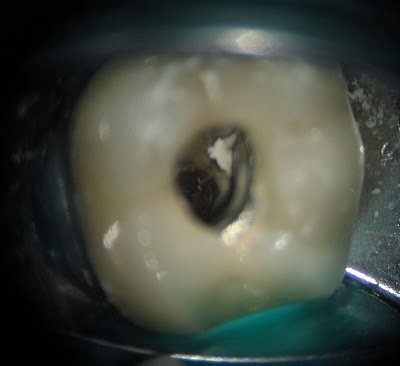

The tooth is deemed non-restorable and extraction recommended.

If you are unsure if a tooth has a cracked/fractured root, contact your endodontist. Not all teeth can be saved, but endodontists are the specialists for saving teeth and can help you determine which ones to save.